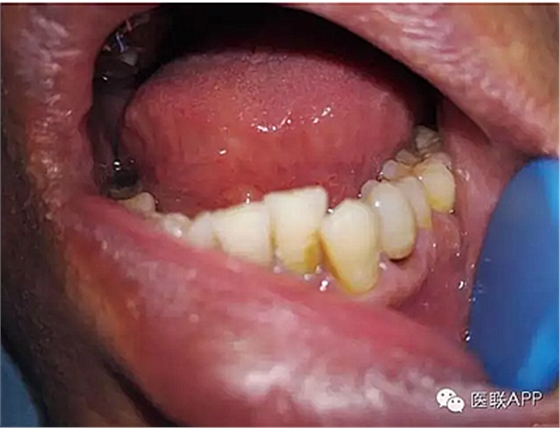

34頰側(cè)楔狀缺損達髓腔,可探及穿髓孔,探痛(-),叩痛(+),松動I度。